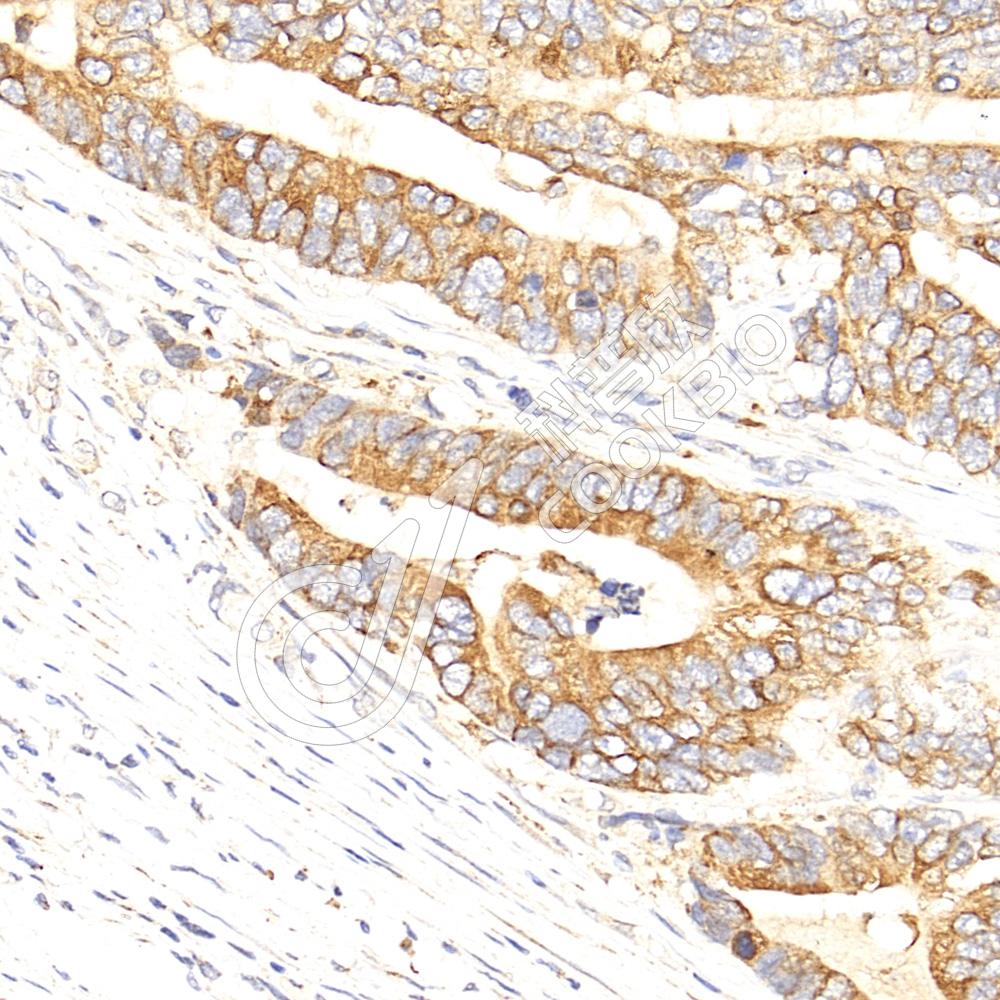

阳性样品:结肠癌, 肺

IHC检测Proteasome 20S beta 6蛋白(货号 K1335853).

样品: 人结肠癌, 4%多聚甲醛 (货号KSG1101) 固定12-24小时.

抗原修复: 柠檬酸抗原修复液(干粉, pH 6.0) (KSG1201), 98℃, 20分钟.

—抗: 1: 900稀释, 4℃ 孵育过夜.

二抗: S-vision免疫组化多聚二抗(山羊抗兔),即用型 (货号KB3906), 室温孵育20分钟.